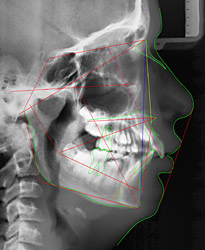

- Röntgenaufnahme des Kopfes von der Seite

Wie sind die Lagen des Oberkiefers und des Unterkiefers?

Wie ist die Neigung der vorderen Zähne im Ober-, und Unterkiefer?